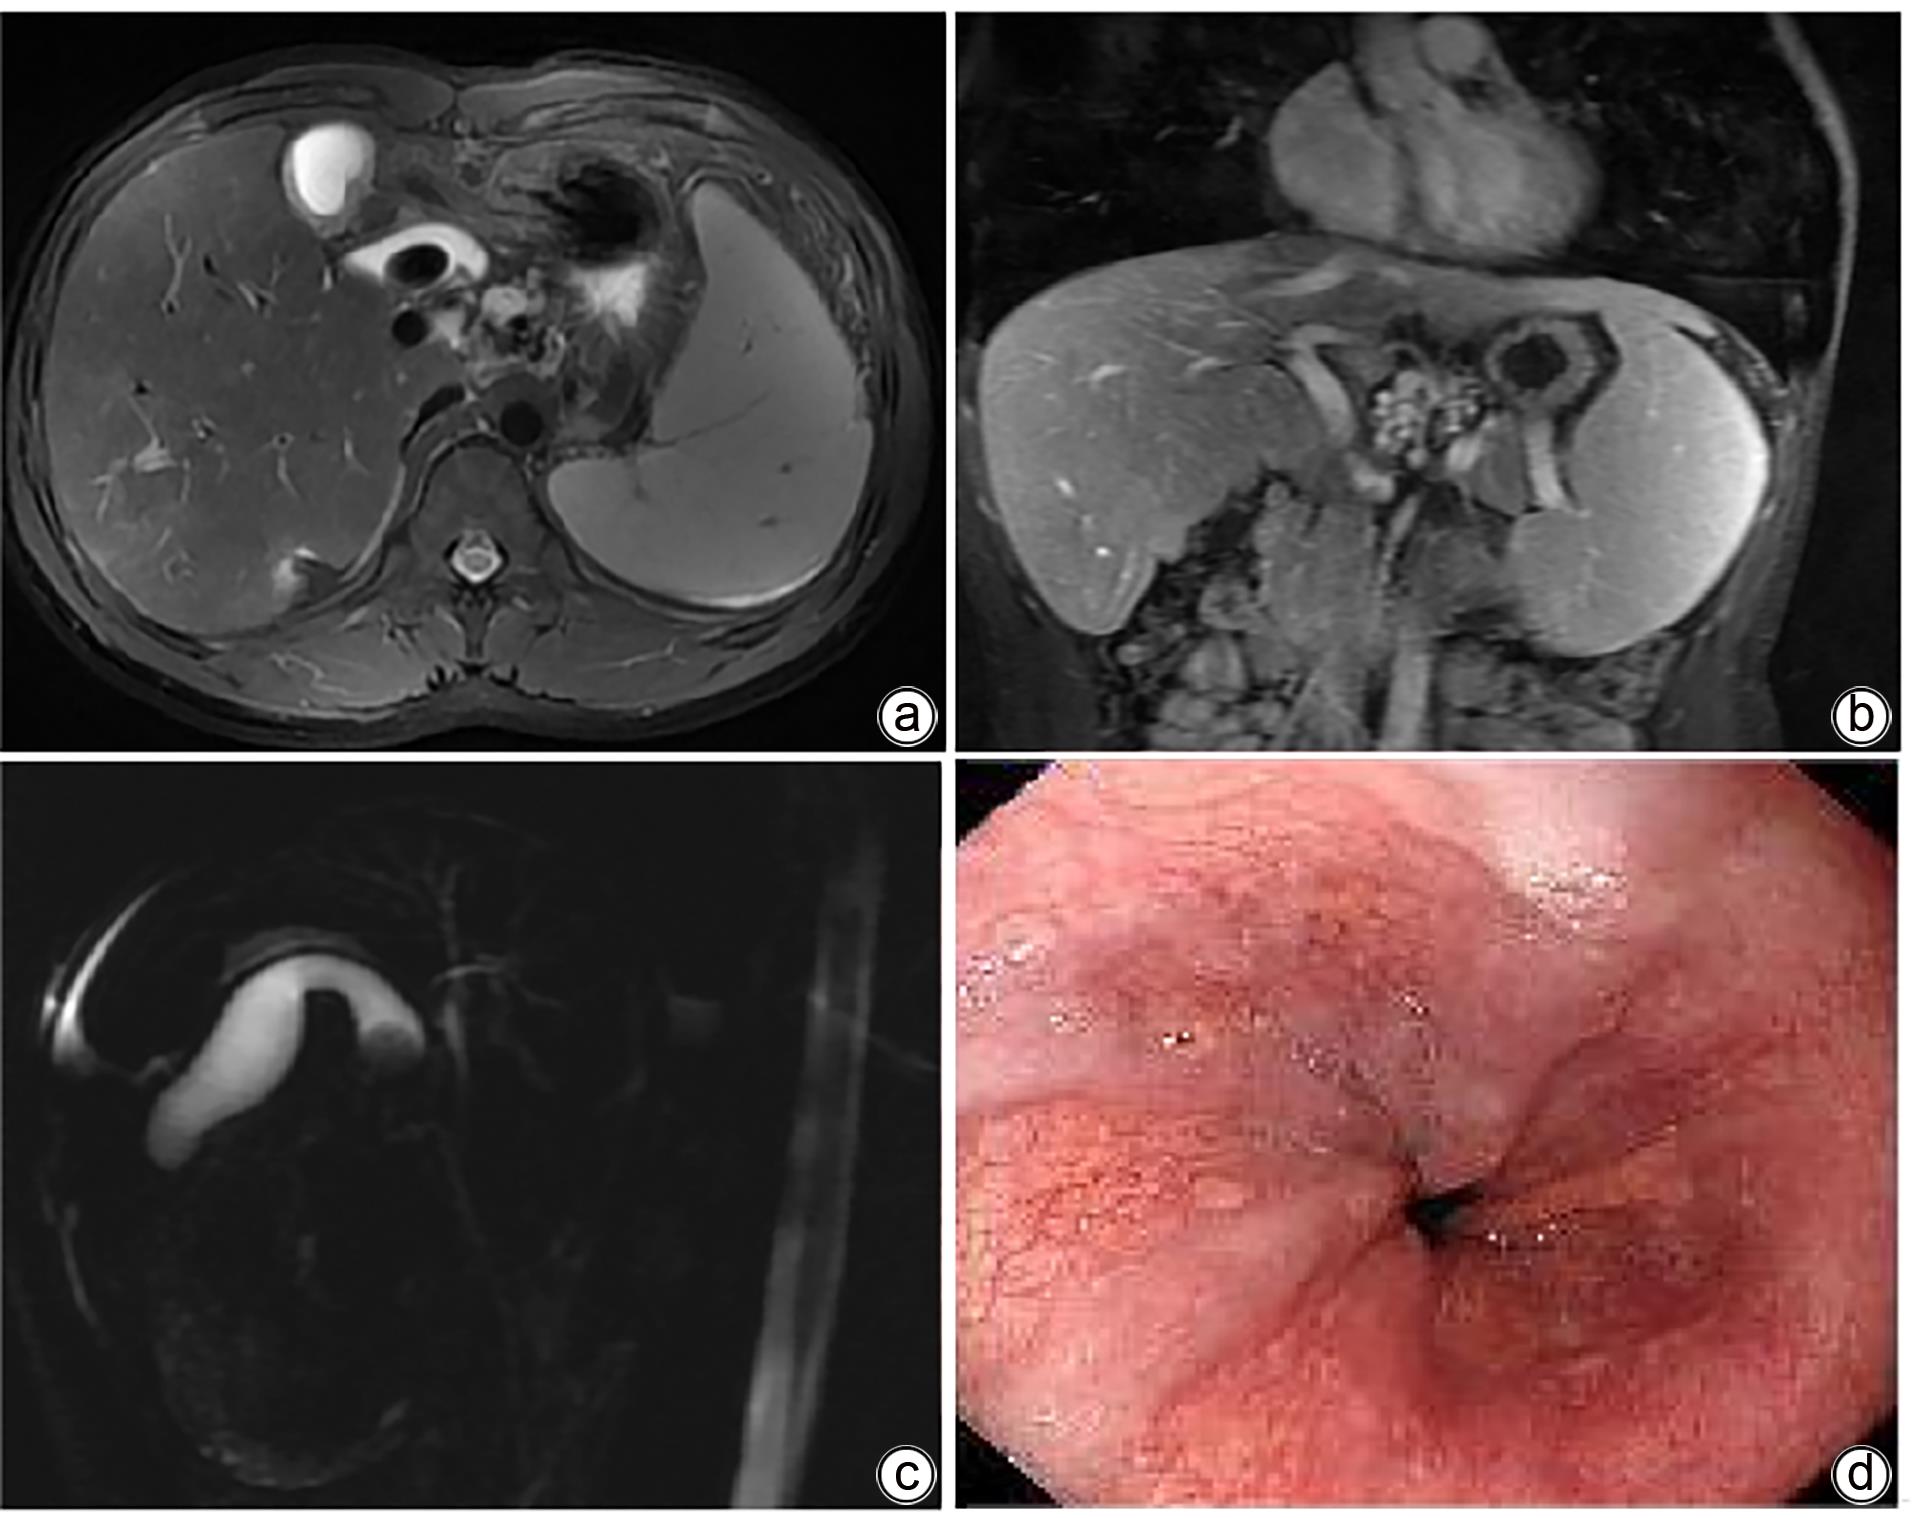

ATP结合盒亚家族B成员4(ABCB4)基因突变相关性肝硬化合并胆囊结石1例报告

刘文迪, 王芃, 胡和平, 周华邦

2024, 40(3): 585-588. DOI: 10.12449/JCH240324

摘要(958) HTML (463) PDF (889KB)(81)

摘要:

ATP结合盒亚家族B成员4(ABCB4)基因突变疾病谱涉及进行性家族性肝内胆汁淤积3型、胆石症、妊娠期肝内胆汁淤积症、门静脉高压、肝硬化,甚至原发性肝脏、胆道恶性肿瘤等多种疾病。本院肝胆内科收治1例青年男性患者,入院初步诊断为胆囊结石,计划腹腔镜胆囊切除术,术前检查发现该患者肝功能异常、肝硬化、脾大、食管静脉轻度曲张,后进一步行二代测序明确诊断为ABCB4基因突变相关性肝硬化合并胆囊结石,给予熊去氧胆酸胶囊利胆治疗后,肝功能逐渐恢复正常。